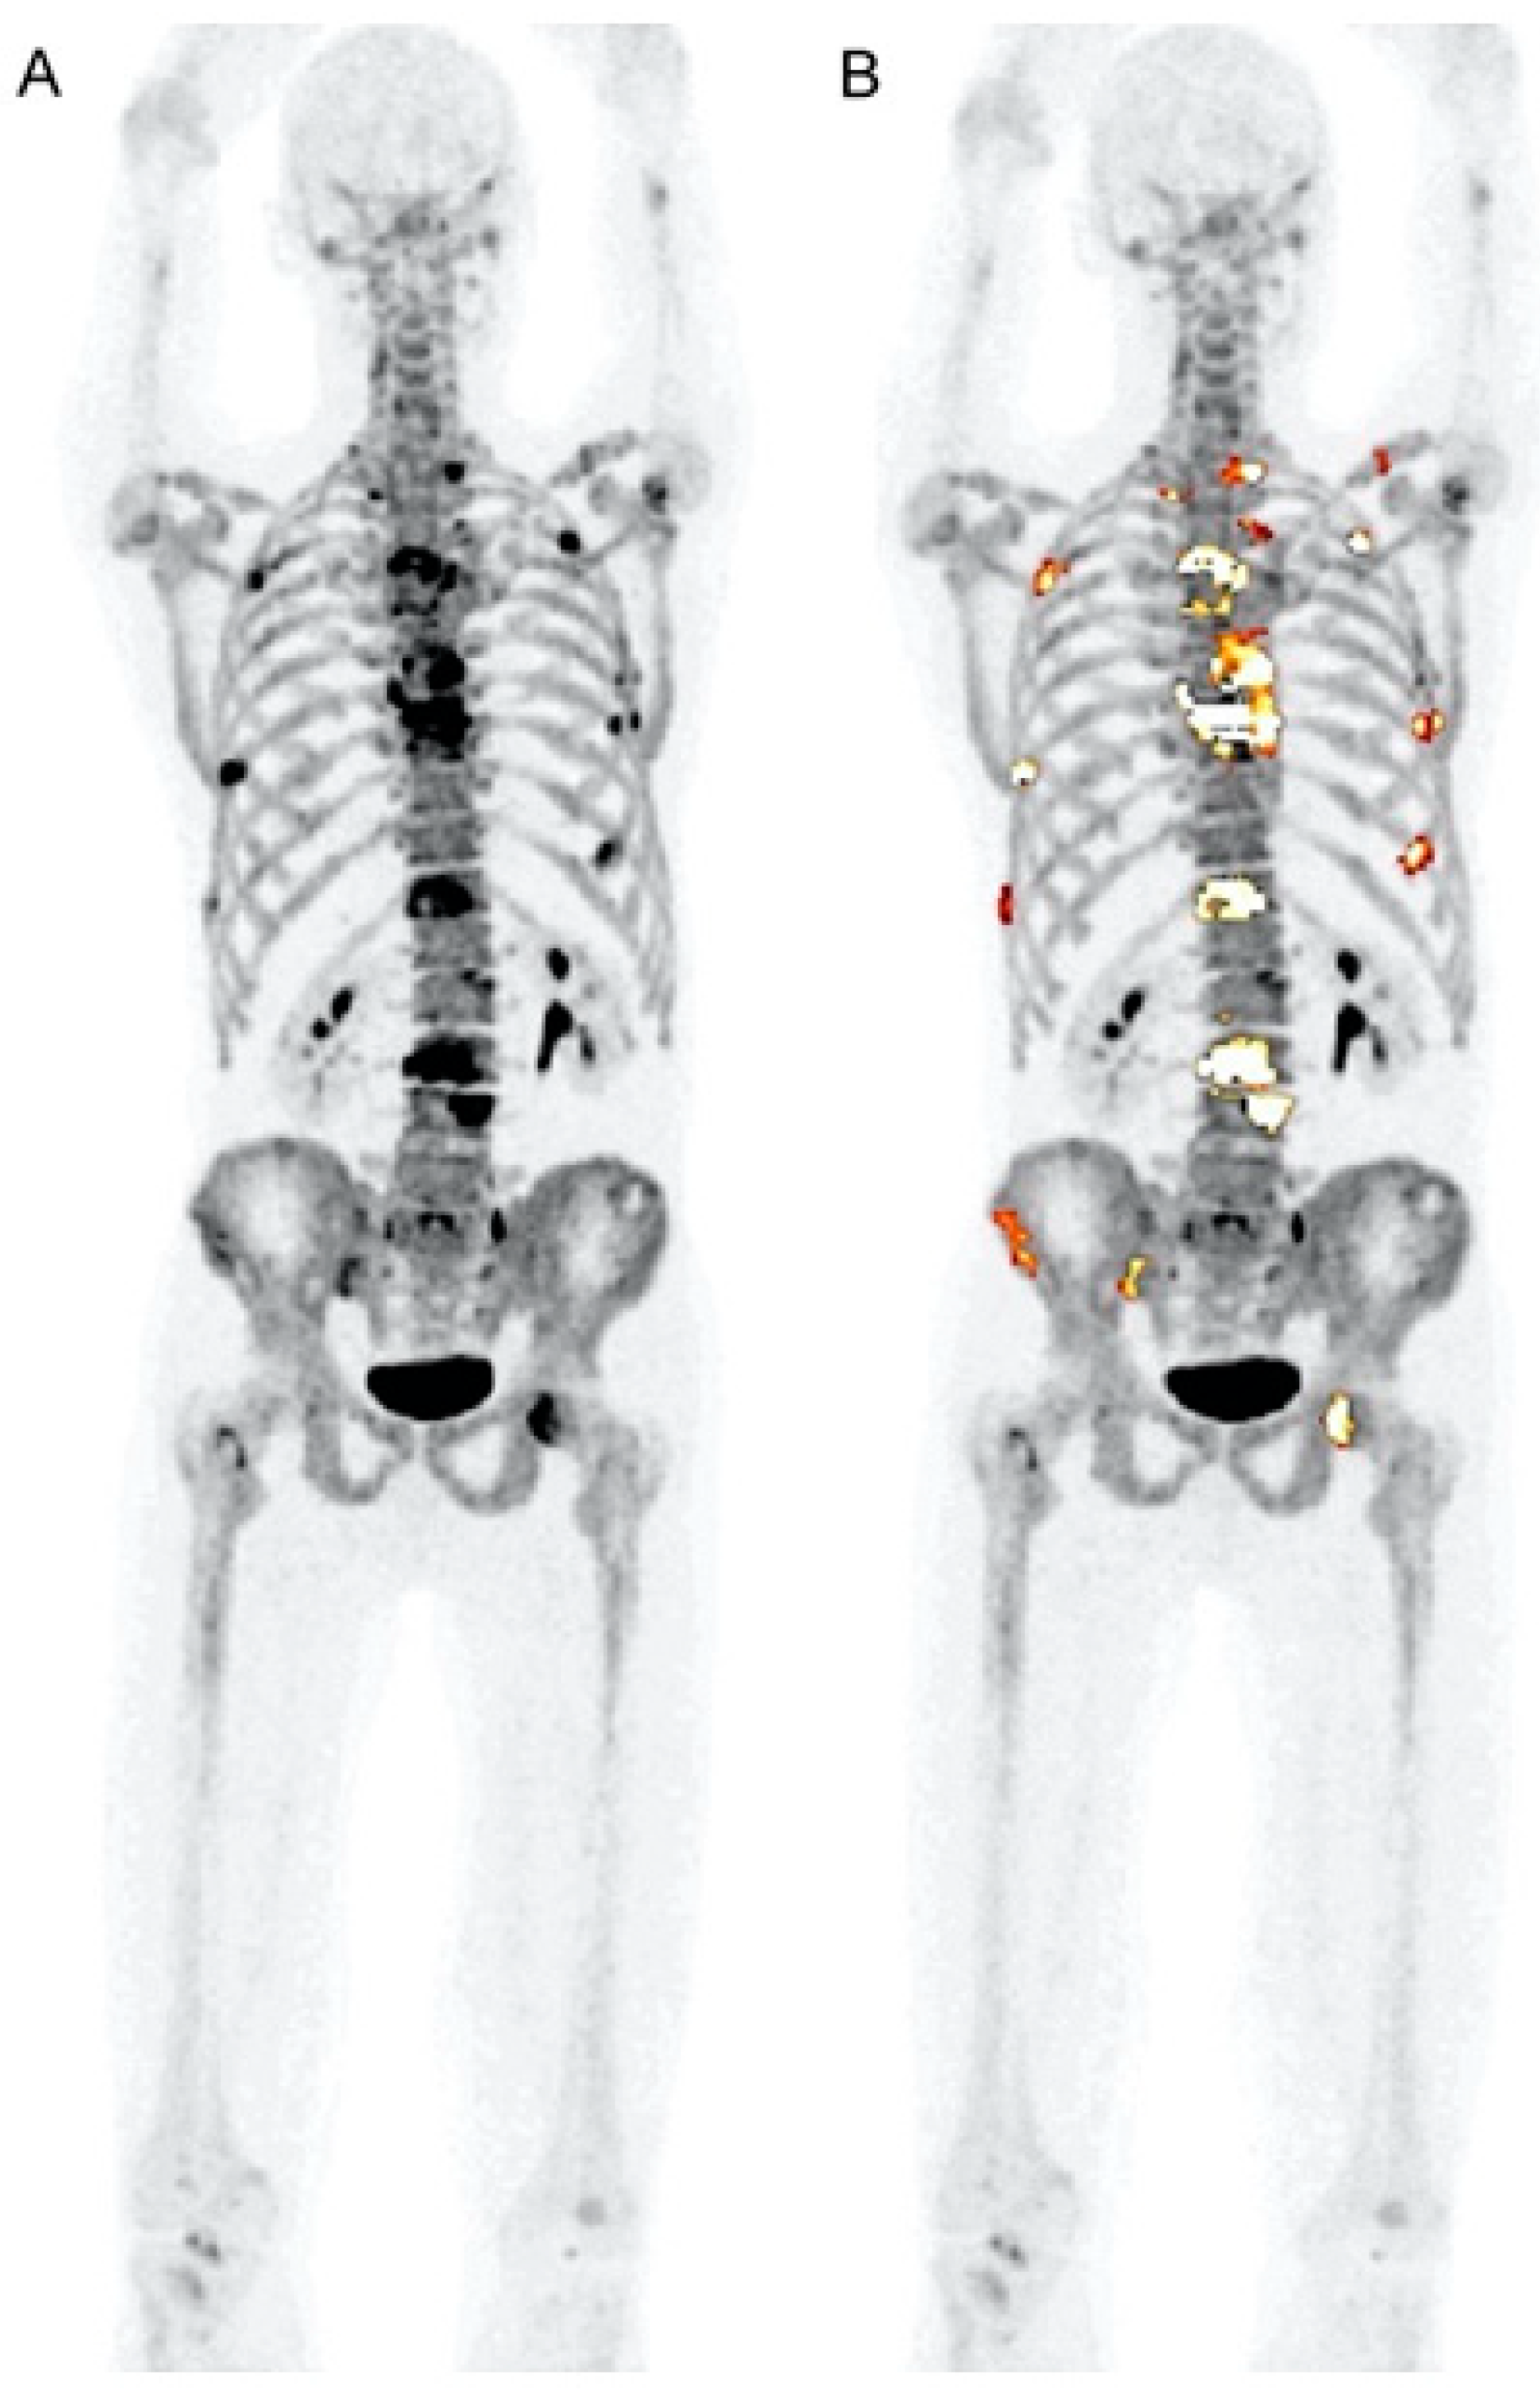

8. PET for Assessment of Bone Turnover in Myeloma Patients

- Zadeh, M.Z.; Seraj, S.M.; Østergaard, B.; Mimms, S.; Raynor, W.Y.; Aly, M.; Borja, A.J.; Arani, L.S.; Gerke, O.; Werner, T.J.; et al. Prognostic significance of 18F-sodium fluoride in newly diagnosed multiple myeloma patients. Am. J. Nucl. Med. Mol. Imaging 2020, 10, 151–160. [Google Scholar]

- Ak, İ.; Onner, H.; Akay, O.M. Is there any complimentary role of F-18 NaF PET/CT in detecting of osseous involvement of multiple myeloma? A comparative study for F-18 FDG PET/CT and F-18 FDG NaF PET/CT. Ann. Hematol. 2015, 94, 1567–1575. [Google Scholar] [CrossRef]

- Sachpekidis, C.; Goldschmidt, H.; Hose, D.; Pan, L.; Cheng, C.; Kopka, K.; Haberkorn, U.; Dimitrakopoulou-Strauss, A. PET/CT studies of multiple myeloma using 18F-FDG and 18F-NaF: Comparison of distribution patterns and tracers’ pharmacokinetics. Eur. J. Nucl. Med. Mol. Imaging 2014, 41, 1343–1353. [Google Scholar] [CrossRef]

- Raynor, W.; Houshmand, S.; Gholami, S.; Emamzadehfard, S.; Rajapakse, C.S.; Blomberg, B.A.; Werner, T.J.; Høilund-Carlsen, P.F.; Baker, J.F.; Alavi, A. Evolving role of molecular imaging with 18F-sodium fluoride PET as a biomarker for calcium metabolism. Curr. Osteoporos. Rep. 2016, 14, 115–125. [Google Scholar] [CrossRef]

- Zirakchian Zadeh, M.; Østergaard, B.; Raynor, W.Y.; Revheim, M.E.; Seraj, S.M.; Acosta-Montenegro, O.; Ayubcha, C.; Yellanki, D.P.; Al-Zaghal, A.; Nielsen, A.L.; et al. Comparison of 18F-sodium fluoride uptake in the whole bone, pelvis, and femoral neck of multiple myeloma patients before and after high-dose therapy and conventional-dose chemotherapy. Eur. J. Nucl. Med. Mol. Imaging 2020, 47, 2846–2855. [Google Scholar] [CrossRef] [PubMed]